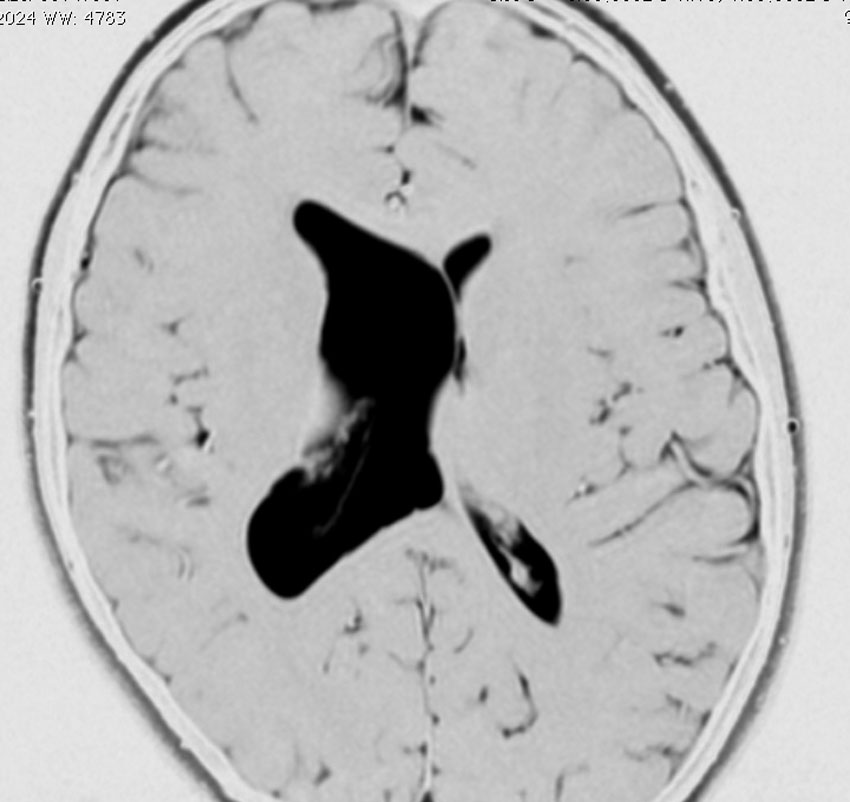

脳室内くも膜のう胞

くも膜のう胞が脳室内にできて,脳室の一部で髄液の流れをさまたげて,部分的な水頭症になることがあります。水頭症になっても停止性水頭症というもので悪化傾向がなければ治療の必要がありません。多くは側頭角というところが拡大するのですが,拡大傾向がはっきりしたら,内視鏡手術でくも膜のう胞の壁を切除します。

これは11歳の子供で偶然発見された右側脳室くも膜のう胞です。無症状で変化しませんからほっておきます。右のモンロー孔に狭窄があるために右側脳室だけの停止性水頭症になっています。